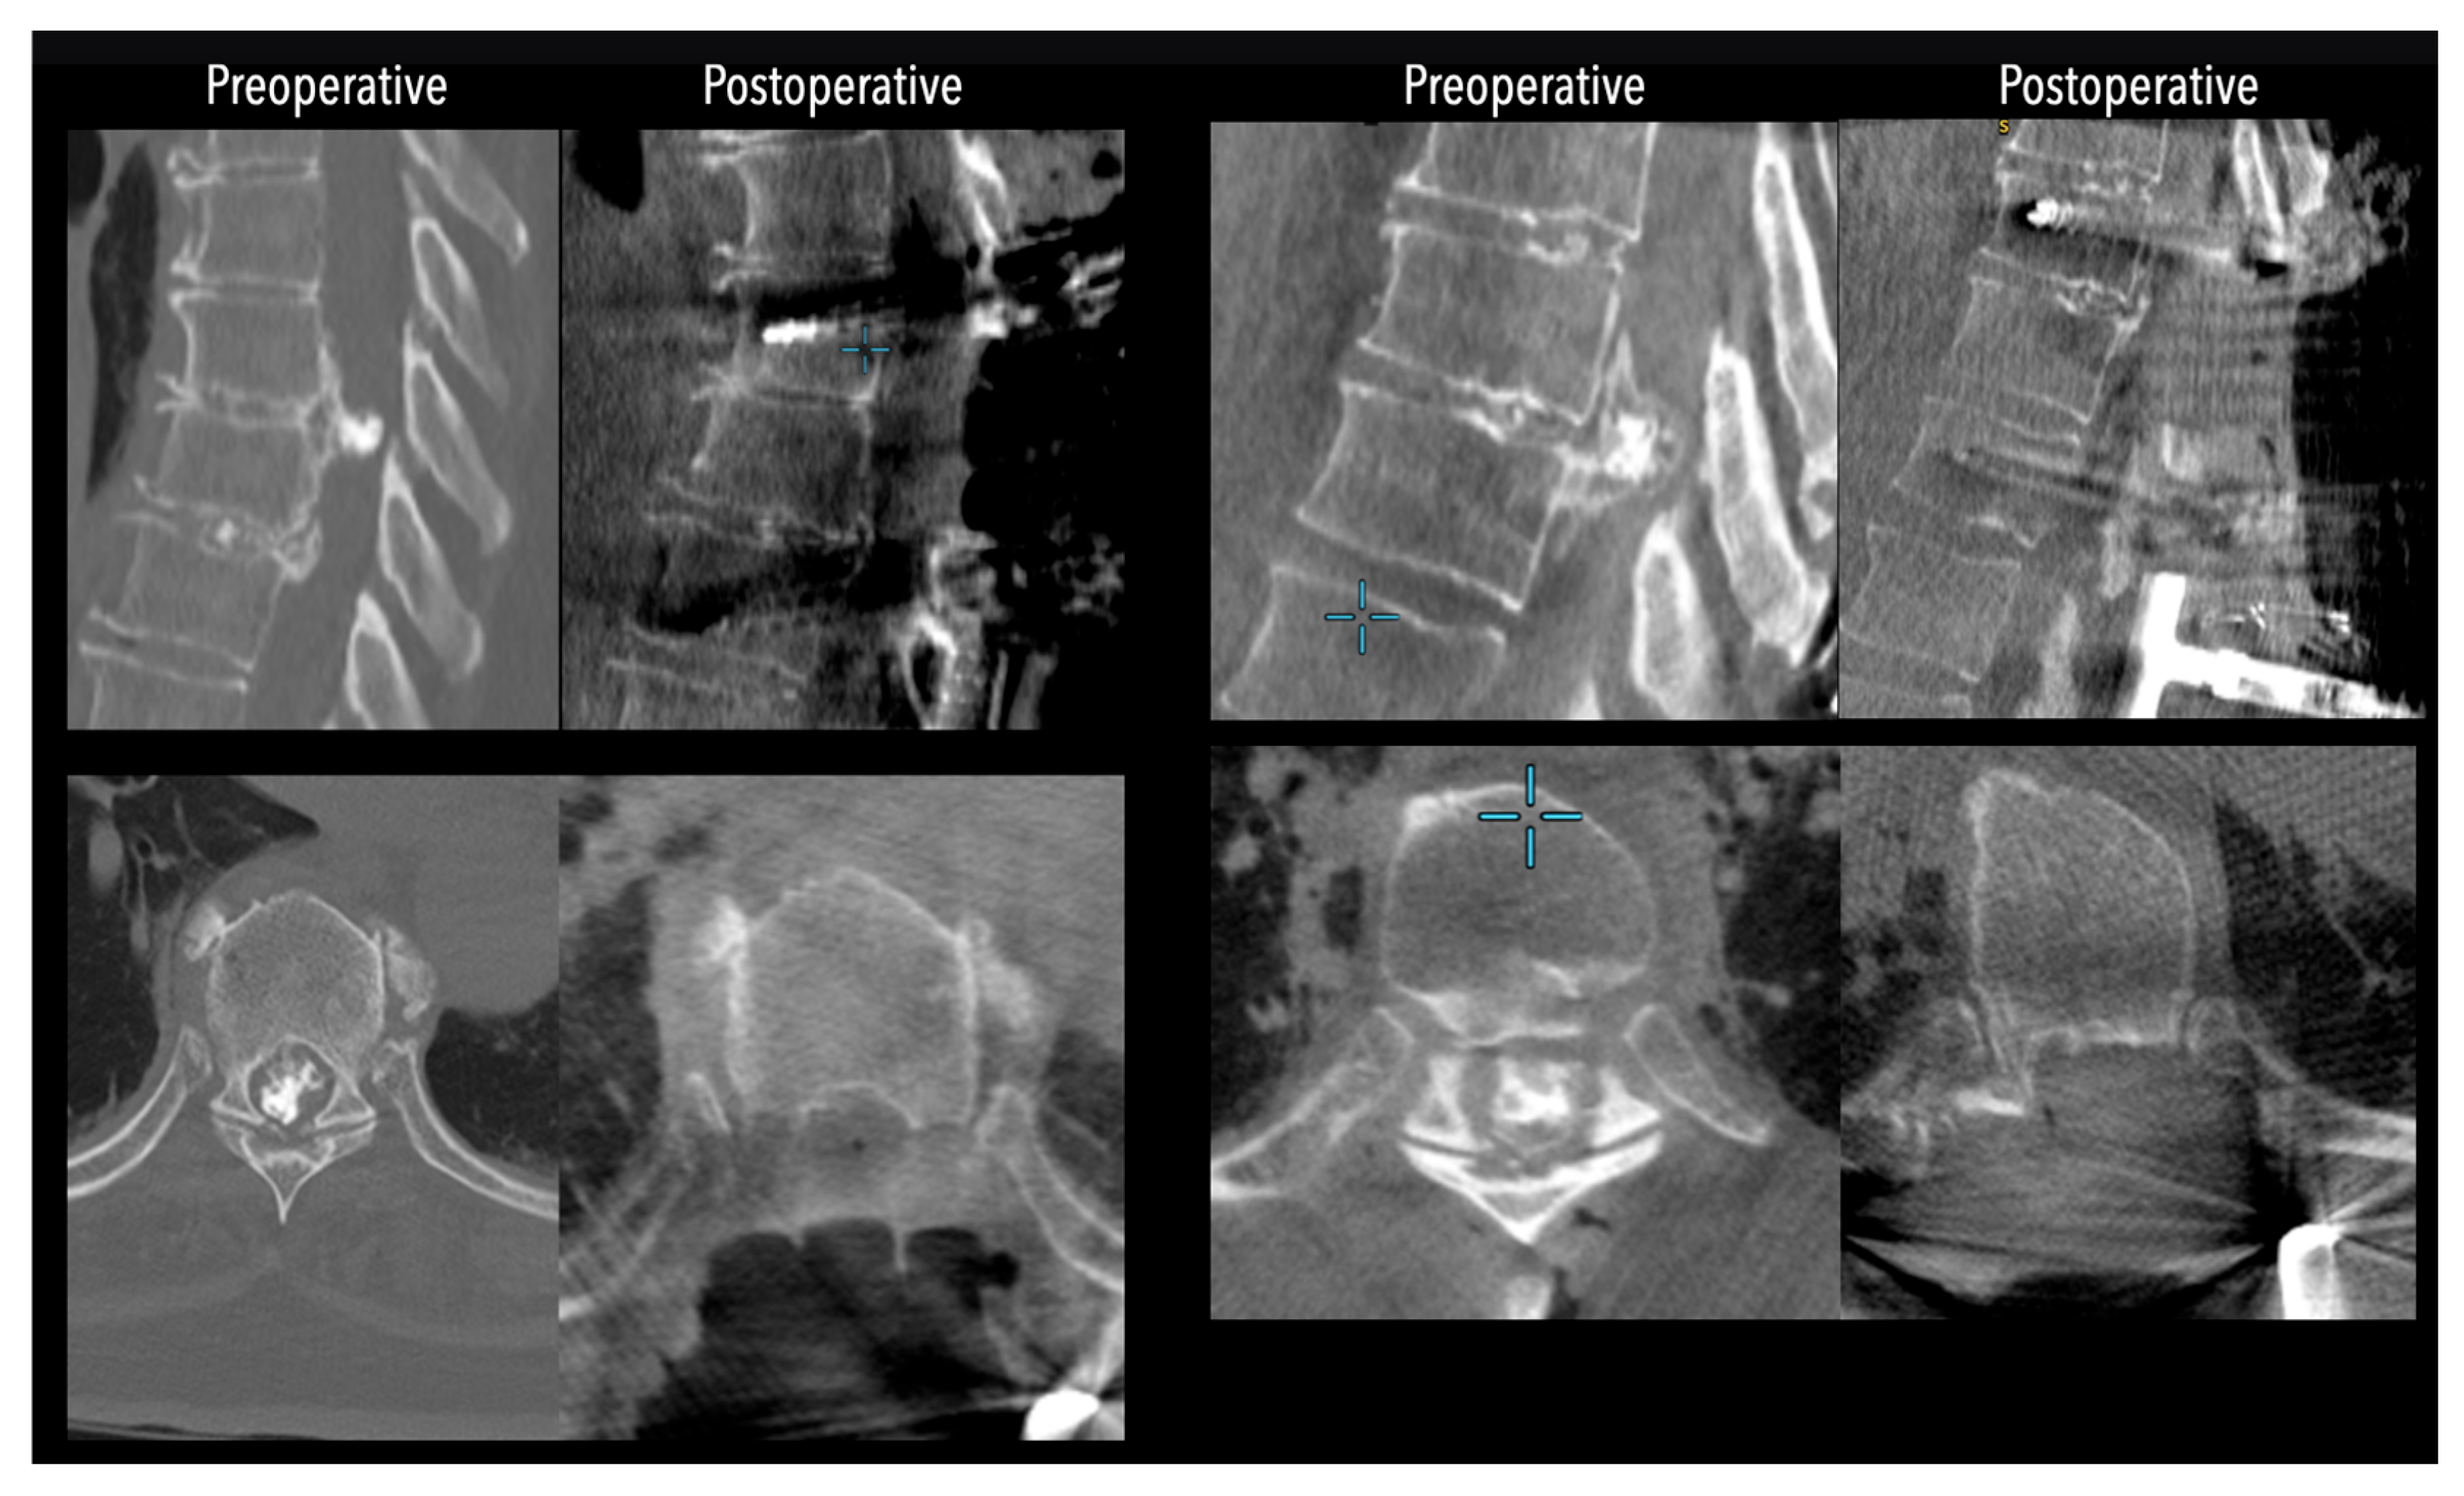

Figure 4. Comparative pre- and postoperative CT scans for two different patients (left and right), illustrating complete discectomy.

In three of the seven cases, the exiting nerve root at the level of the herniation was ligated due to poor visualization and transected extradurally to improve access. In the remaining four patients, the nerve root was either preserved or dissected intradurally using isocool bipolar diathermy and microsurgical scissors. With gentle medial retraction of the cord under gravity and protection using a micro-patty, the calcified disc was exposed. The ventral dura, when intact, was incised sharply and dissected from the disc surface where possible (Figure 2a,b and Figure 3). Disc removal was performed using a hockey-stick-shaped Misonix bone scalpel with constant irrigation, guided by intraoperative neuronavigation. The disc material was resected to a depth of 1–2 mm beyond the posterior vertebral wall to ensure adequate decompression. A second O-Arm spin was routinely performed following discectomy to confirm satisfactory decompression, especially given the limitations of the postoperative MRI due to the metal artefact (Figure 4, Figure 5 and Figure 6).